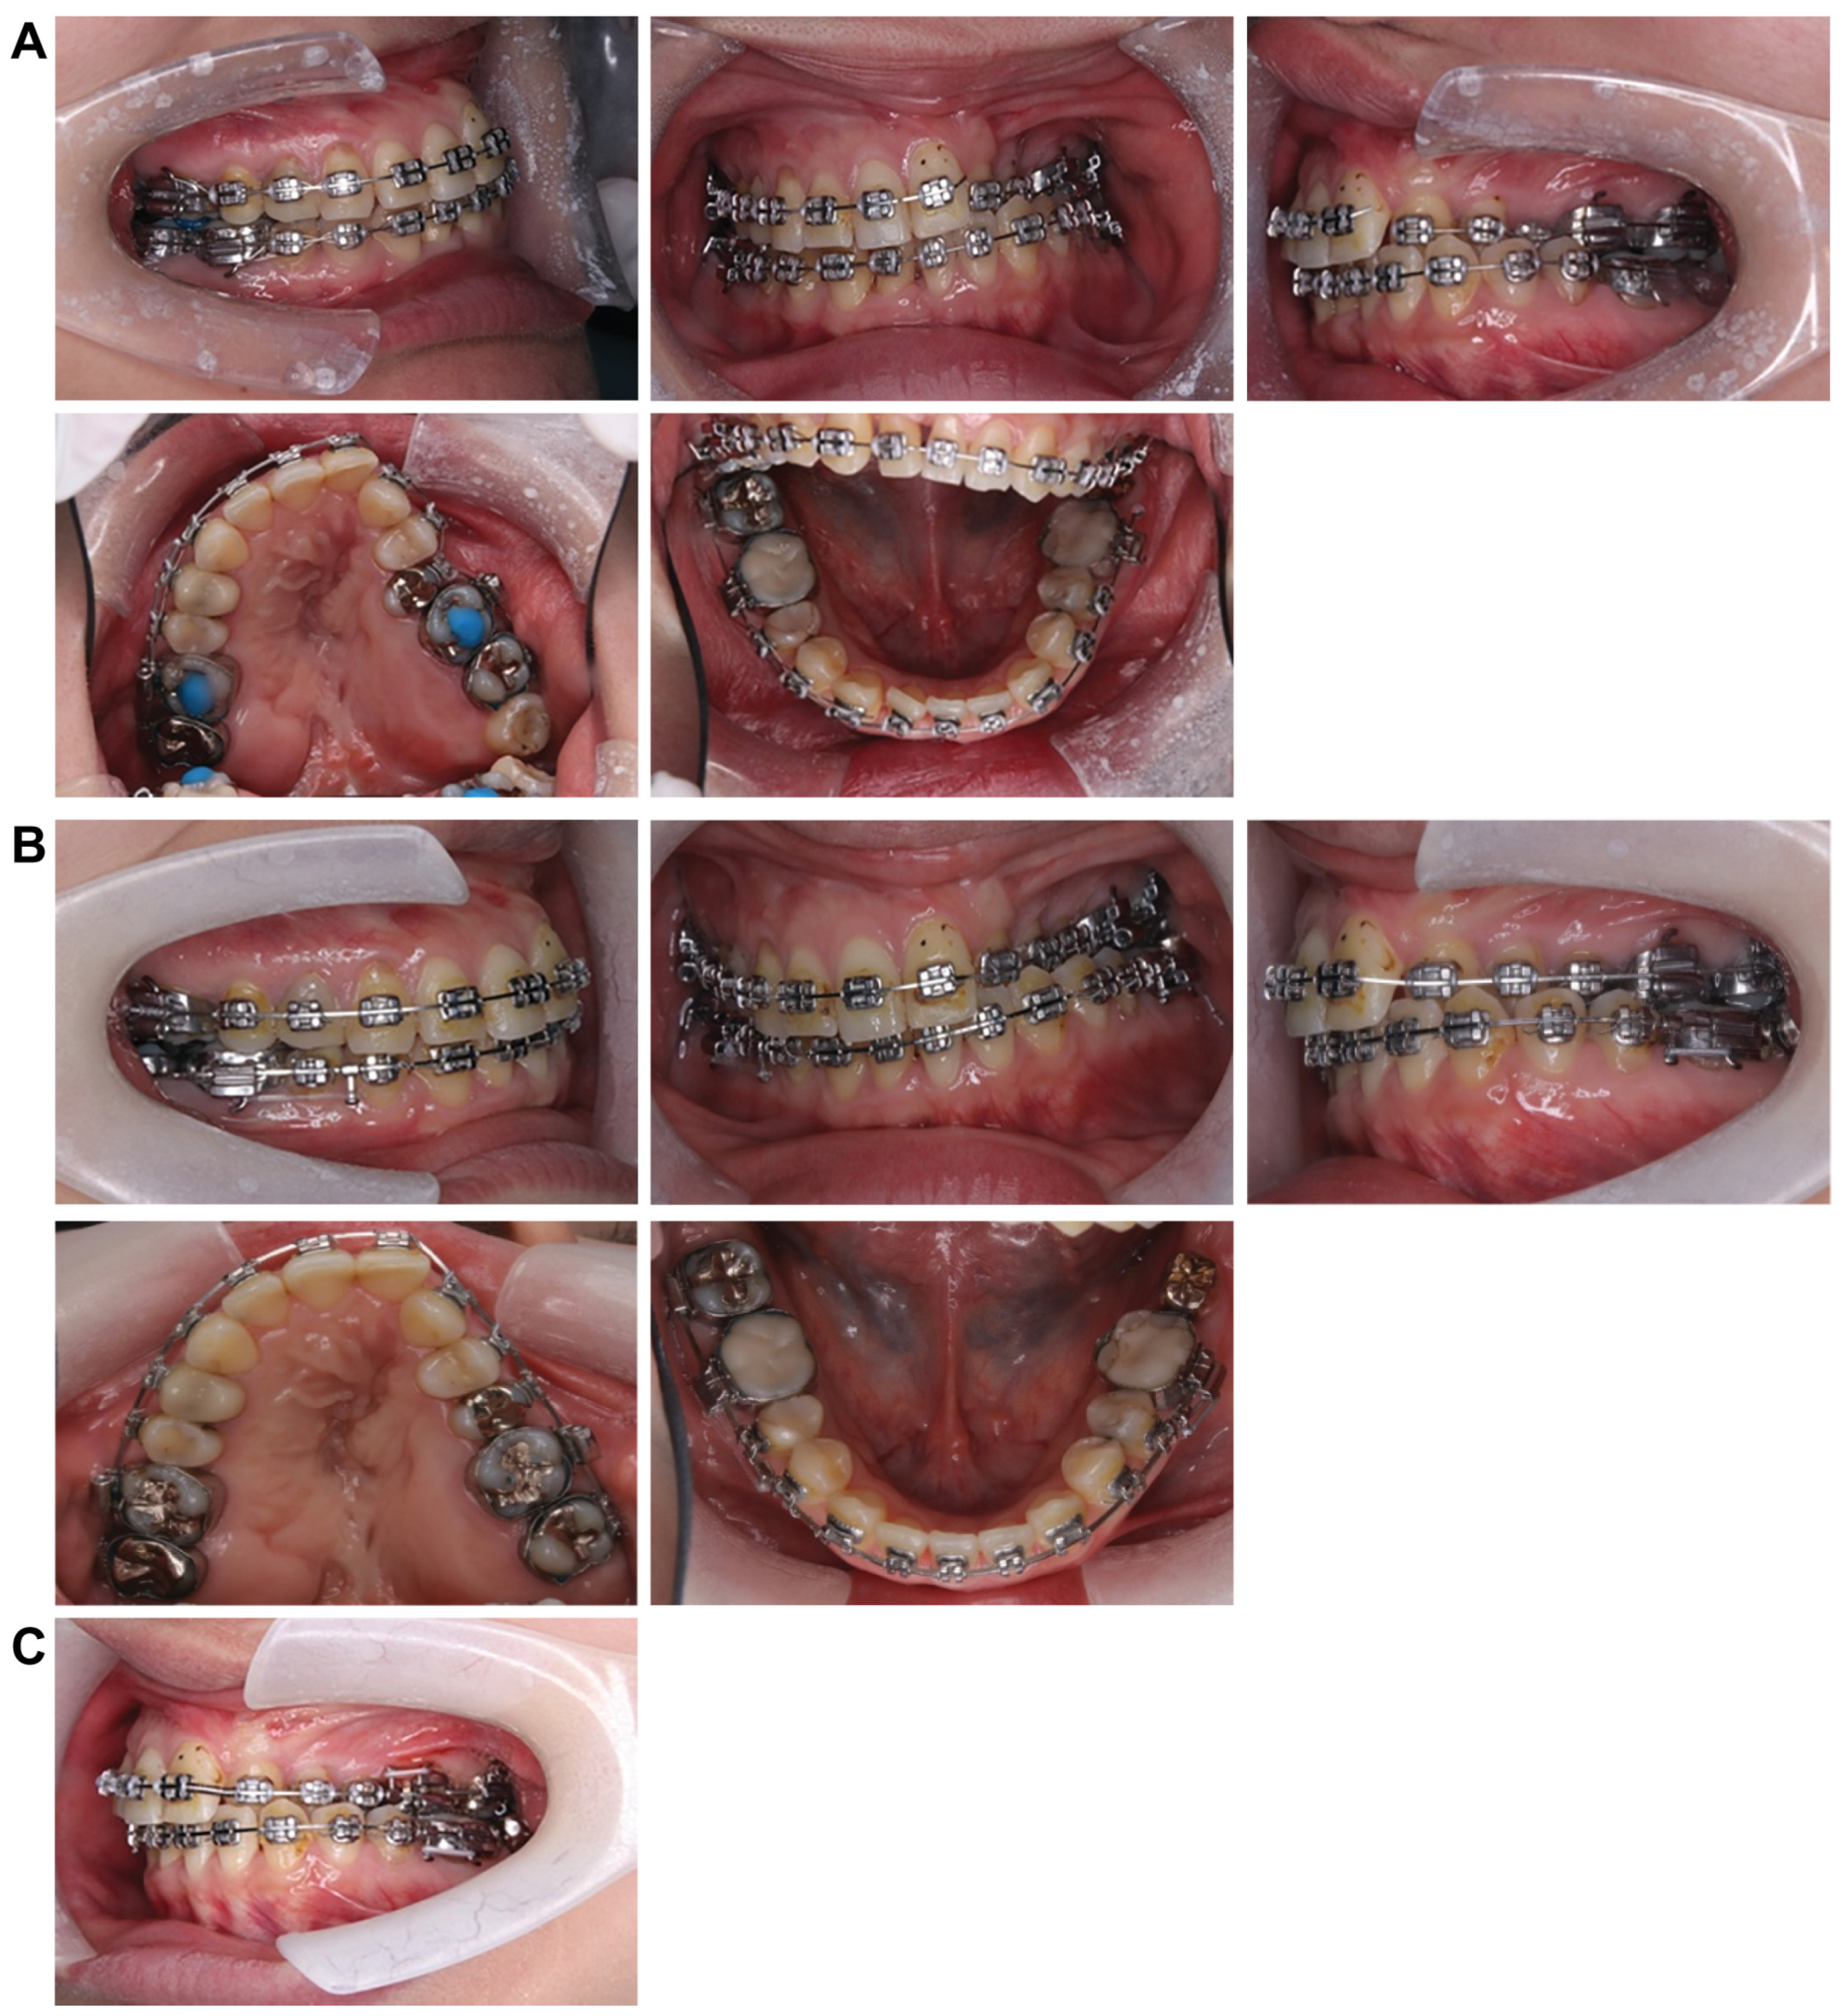

Treatment progress: During preoperative orthodontic treatment, owing to the significant asymmetry in the left and right maxillary dental arches, leveling was initiated using a sectional arch, dividing the maxilla into two segments: from the right second molar to the left central incisor and from the left canine to the left second molar. The mandibular right lateral incisor, which exhibited lingual displacement, was extracted, and a multi-bracket device (0.022 slot pre-adjusted appliance) was placed. After leveling was completed in the maxilla, the treatment transitioned to a continuous arch to minimize intraoperative movement while improving the arch width. Subsequently, to facilitate the multi-segment Le Fort I osteotomy, an open coil spring was placed between the left central incisor and the canine to gain the necessary osteotomy width. In the mandible, the extraction space from the right lateral incisor was used to improve crowding and space closure was performed (Figure 5). Dental photographs taken just before surgery confirmed that a 3.0 mm space was achieved for the surgical procedures necessary for the multi-segment approach, at which point the arch was switched to a sectional arch (Figure 6). After 15 months of treatment, preoperative orthodontics were nearly completed, and preoperative records were obtained. Crowding in the mandible was resolved, and the arch of the maxilla approached an ovoid shape with approximately 4.0 mm of expansion in width; however, the occlusion on the right side remained a crossbite (Figure 7). During orthognathic surgery, a rolling movement of 6.0° to the right was performed around the left first molar to correct the left-sided cant of the occlusal plane. A 5.0° posterior impaction centered on the anterior nasal spine and a 2.0 mm parallel shift to the left were also performed to improve the deformity and align the midline. Furthermore, a multi-segment Le Fort I osteotomy was performed to expand the maxilla by 5.0 mm from the left canine to the second molar, correcting the maxillary and mandibular arch asymmetry. During this process, a releasing incision was made at the palatal scar site, using a chisel and mallet for osteotomy.

Figure 5.

Treatment progress. (A) Attach nickel titanium wires to the upper and lower jaws and begin leveling. (B) After extracting the mandibular right lateral incisor, attach an angle wire and continue to level. (C) Contain the upper maxilla wire and improve the width and diameter.

Figure 6.

An open coil creates a space between the upper right central incisor and canine to create a gap for the bone chisel.

Figure 7.

Preoperative intraoral photograph and radiographs and CT. (A) Intraoral photographs. (B) Panoramic radiograph. (C) Cephalograms and CT.

In the mandible, SSRO was performed, involving an 8.0° right rolling movement and a 2.0 mm parallel movement to the left to correct the deviation. In addition, to address the protrusion of the lower lip, a setback of 4.0 mm was performed to enhance the facial profile. Postoperatively, surgical splinting and intermaxillary fixation were performed. For bone fixation of the maxilla and mandible, titanium plates were used, with horizontal plate fixation implemented in the maxilla to improve the bone width (Figure 8). Notably, for 5 months postoperatively, intermaxillary elastics were used to stabilize the occlusion, and the multi-bracket system was removed 14 months post-surgery. During this period, at the patient’s request, a splint retainer was fabricated, and the brackets were removed to commence the retention phase.

Figure 8.

Under surgical orthodontic treatment.